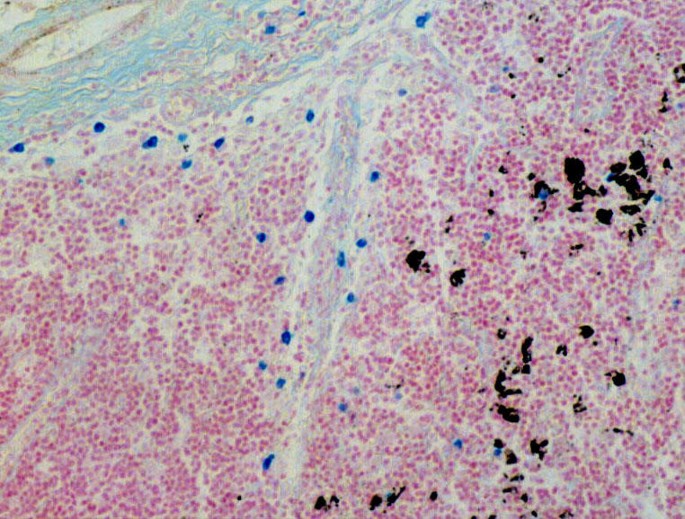

Mast cells were observed in the subcapsular sinus, paracortical areas, medullary cords, and medullary sinus (Figure 1) and were rarely seen in the B cell area. The mast cell count in tumor-free mediastinal lymph nodes (33.23 ± 24.58) of lung cancer patients was significantly higher than in lymph nodes showing metastasis (19.78 ± 12.76, and 9.69 ± 9.37 in group B and C respectively; group A vs. B: P = 0.0155; group B vs. C: P = 0.0064; group A vs. C: P = 0.0019). Metastatic lymph nodes had very few mast cells. This trend was observed in patients with both adenocarcinoma and squamous cell carcinoma. However the groups are too small to have meaningful separation.

In cancer-positive nodes, mast cells were observed primarily around tumor deposits with an occasional mast cell seen within the metastatic foci.